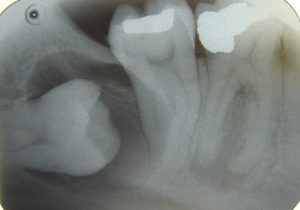

Most people still possess the terminal molars, also known as...

In general practice the dentist will normally examine you radiographically...